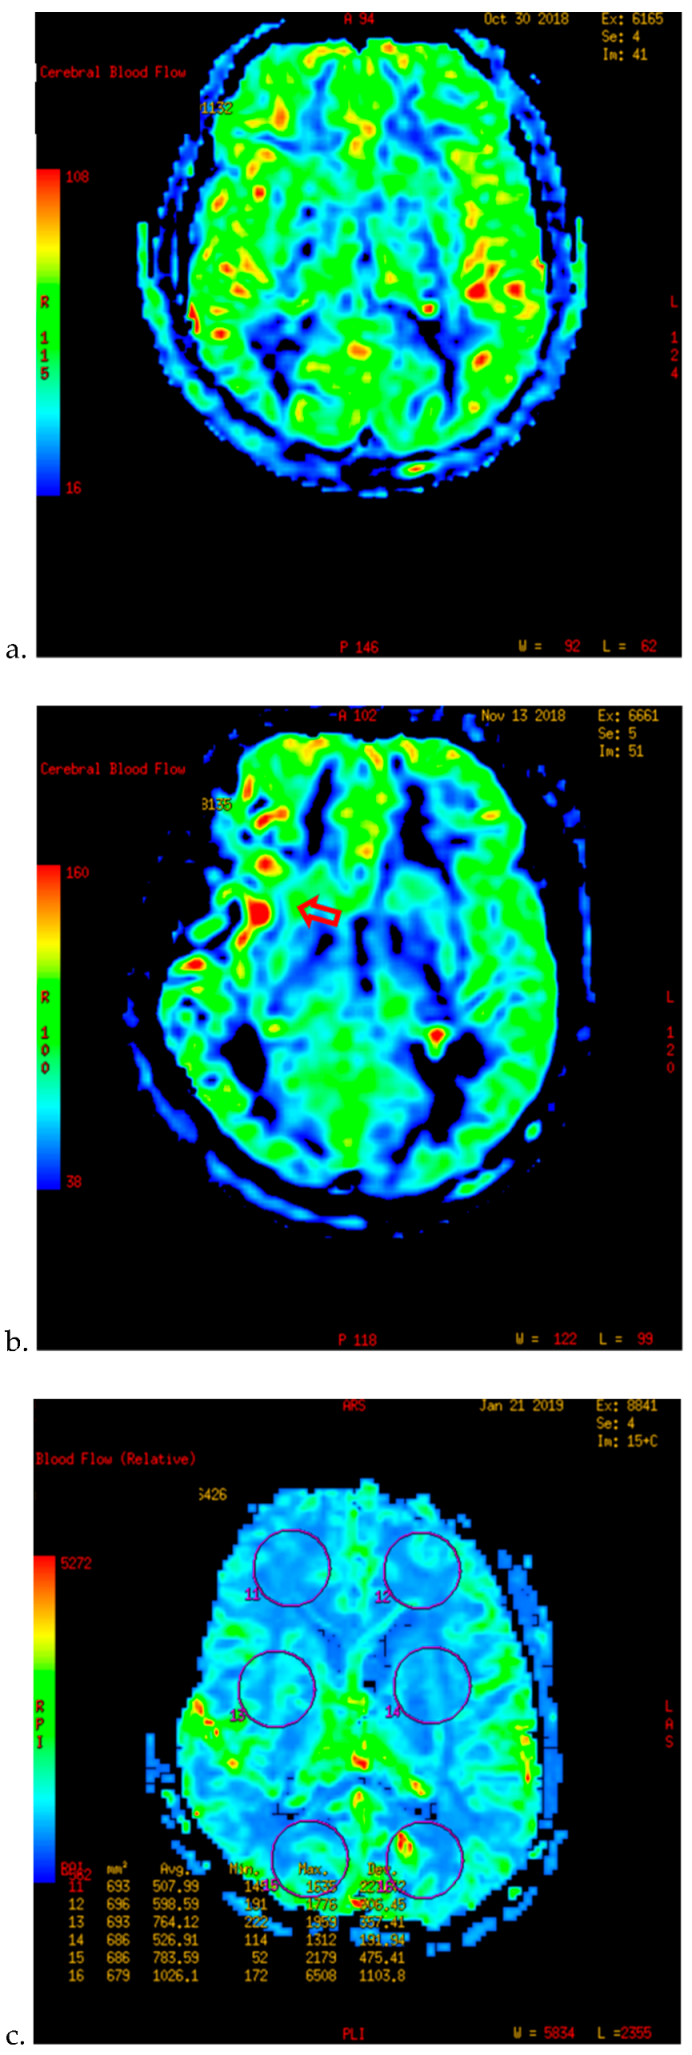

- Kameyama, M.; Fujimura, M.; Tashiro, R.; Sato, K.; Endo, H.; Niizuma, K.; Mugikura, S.; Tominaga, T. Significance of Quantitative Cerebral Blood Flow Measurement in the Acute Stage after Revascularization Surgery for Adult Moyamoya Disease: Implication for the Pathological Threshold of Local Cerebral Hyperperfusion. Cerebrovasc. Dis. 2019, 48, 217–225. [Google Scholar] [CrossRef]

- Tu, X.K.; Fujimura, M.; Rashad, S.; Mugikura, S.; Sakata, H.; Niizuma, K.; Tominaga, T. Uneven cerebral hemodynamic change as a cause of neurological deterioration in the acute stage after direct revascularization for moyamoya disease: Cerebral hyperperfusion and remote ischemia caused by the ‘watershed shift’. Neurosurg. Rev. 2017, 40, 507–512. [Google Scholar] [CrossRef]